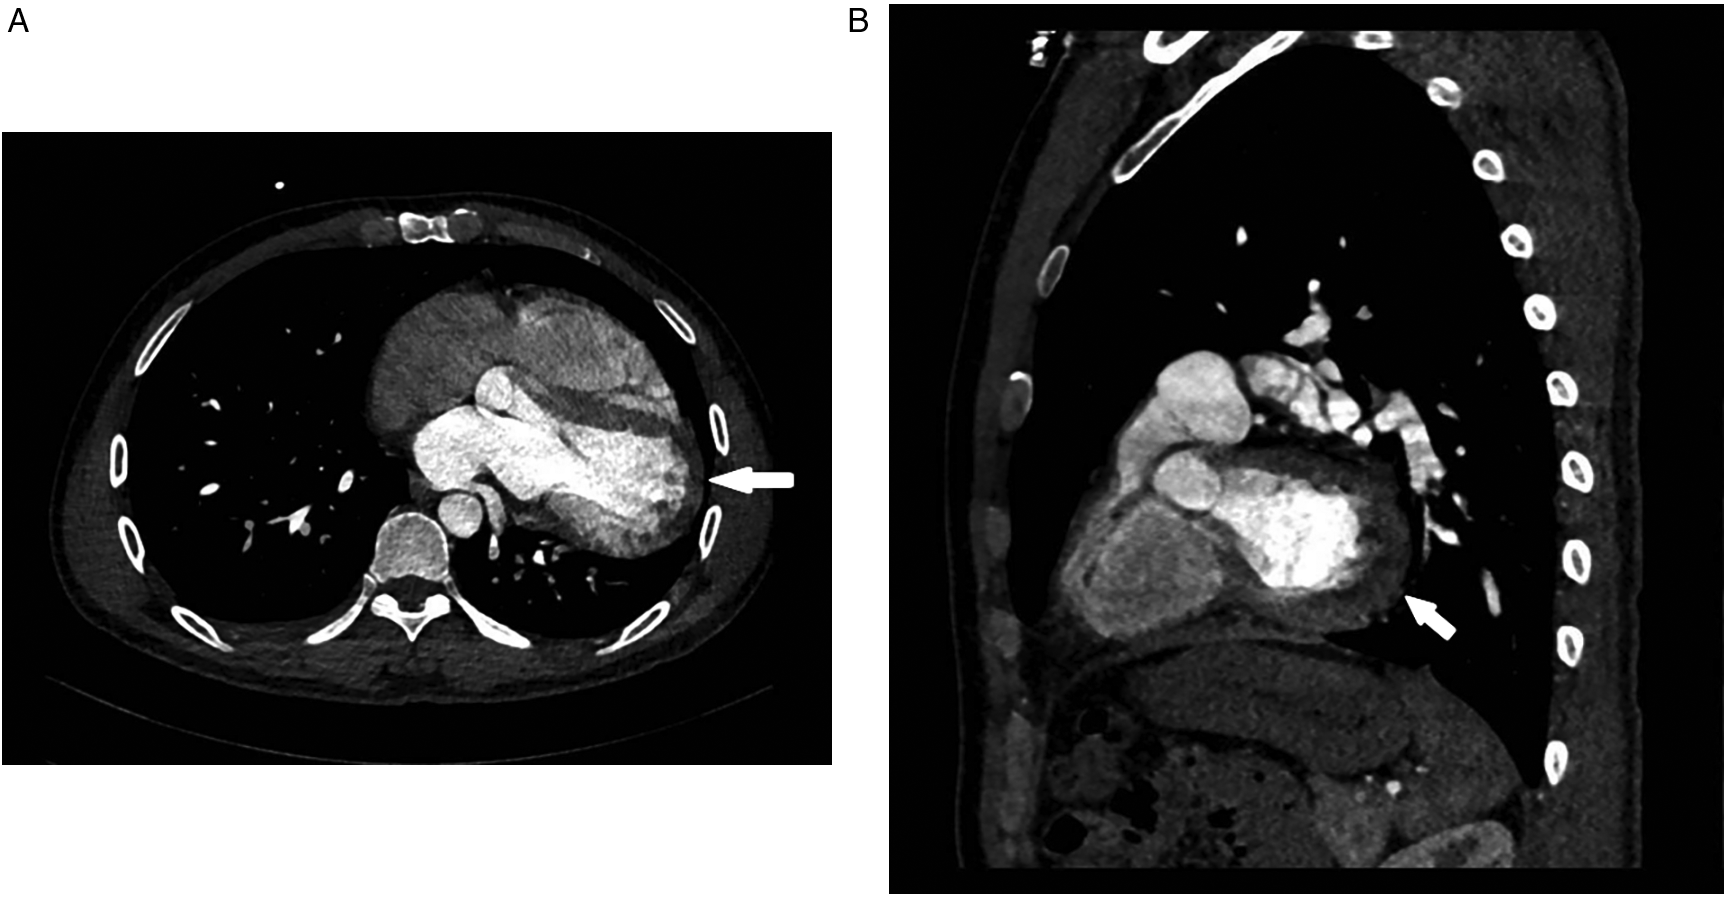

Despite initial imaging suggesting PE, persistent symptoms and negative D-dimer levels contradict typical PE progression. Repeat CT angiography revealed right ventricular enlargement and mild left lower pulmonary vein narrowing (Figure 1C). A lung perfusion scan revealed a small wedge-shaped perfusion defect in the dorsal segment of the left lower lobe, suggesting pulmonary embolism (Figure 1D). Right heart catheterization revealed normal pulmonary artery pressure and vascular resistance. Pulmonary angiography revealed no filling defects or branch truncations in the right pulmonary artery (Pulmonary flow grade 3) or left pulmonary artery. However, delayed contrast flow in the left lower pulmonary artery and venous return (Pulmonary flow grade 2) provided insufficient evidence for pulmonary embolism (5). A multidisciplinary team review revealed leftward cardiac rotation, discontinuity of the left pericardium (Figure 2), and left atrial compression of the lower pulmonary vein, which were consistent with CAP. Given the mild symptoms and low degree of herniation risk, conservative management with follow-up was chosen. At 3-month follow-up (July 2025), the patient remains asymptomatic. This case uniquely highlights pulmonary venous compression due to cardiac displacement-a previously unreported manifestation of CAP-suggesting its clinical variability.

Figure 2

Ct angiography [axial (A), sagittal (B) planes]: absence of the left pericardium.